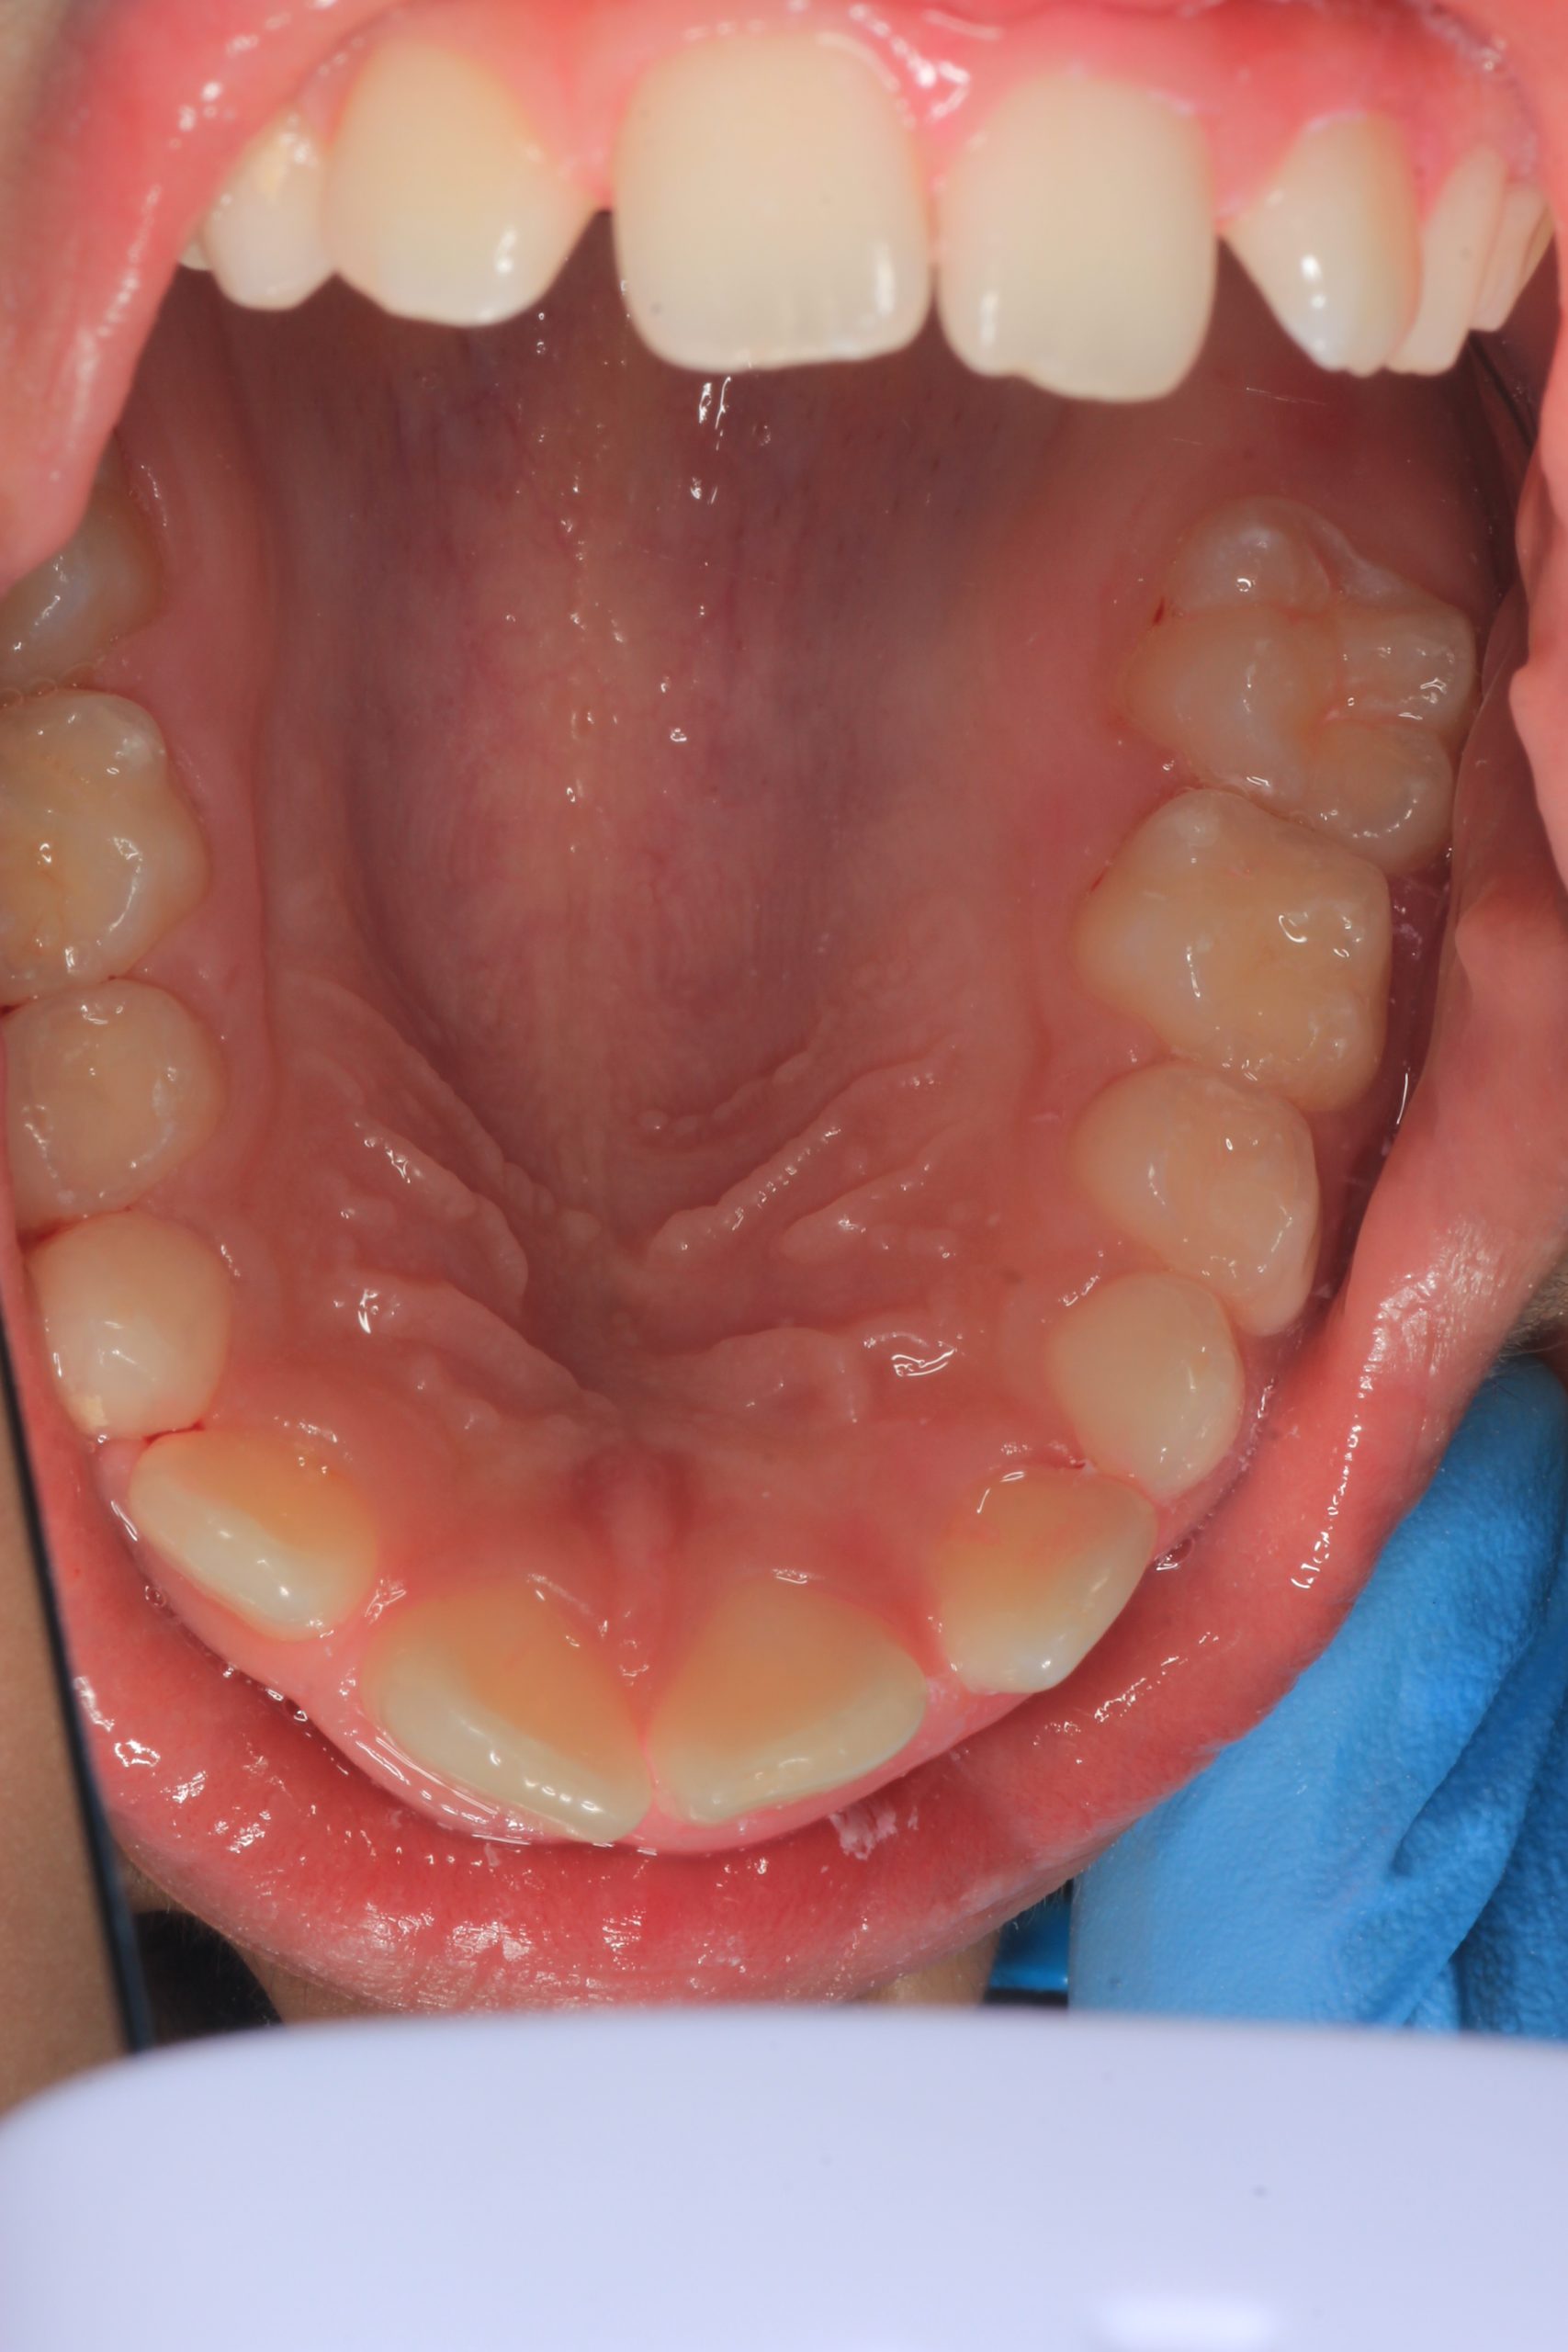

We examine the condition of teeth, gums, and bite. - Plaque Disclosure with Special Indicators

Areas that weren’t cleaned well appear purple. The darker the shade, the older the plaque. This helps both kids and parents understand where brushing needs to improve. - Brushing Training & Home Care Tools Selection